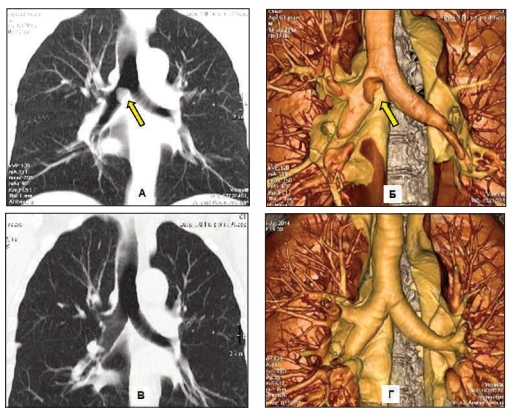

1. Severe lung damage - a life without breath

Over time, chronic inflammation and toxin buildup cause irreversible damage to the airways and lung tissue.

The lungs lose their ability to absorb oxygen efficiently. No quick remedy can restore what's been destroyed.

Untreated lung congestion and airway inflammation often develop into full-scale COPD.

It may begin with mild shortness of breath or an occasional cough-but the damage continues silently.

Before patients realize what's happening, their lung capacity has already declined significantly.